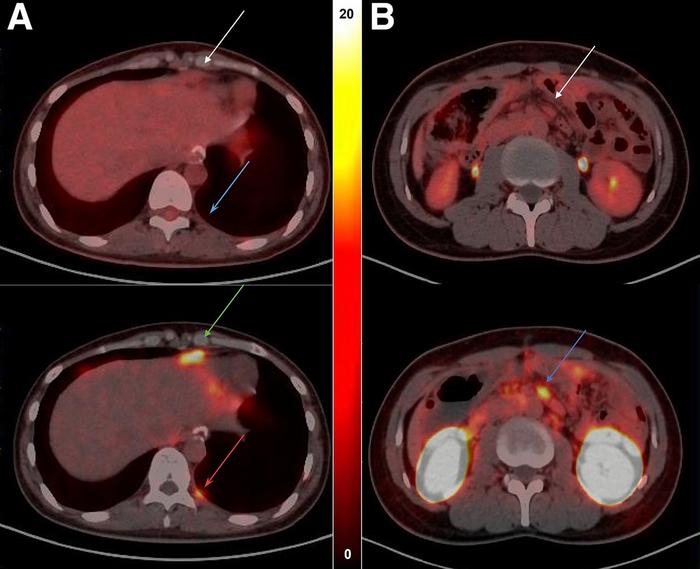

Researchers first synthesized the radiotracer 68 Ga-NC-BCH and performed preclinical evaluations on human gastrointestinal cancer cell lines and mouse models. Next, 11 patients underwent whole-body 68 Ga-NC-BCH PET and 18 F-FDG PET, and radiopharmaceutical biodistribution, radiation dosimetry, and the relationship between uptake and CLDN18.2 were evaluated.

68 Ga-NC-BCH was stably prepared and demonstrated good radiochemical properties. The radiotracer exhibited rapid blood clearance, high affinity for CLDN18.2, and high specific uptake in CLDN18.2-positive cells and xenograft mouse models. In patients, 68 Ga-NC-BCH displayed high uptake in the stomach and kidney and slight uptake in the pancreas. Compared with 18 F-FDG, 68 Ga-NC-BCH identified more lesions in the lymph nodes and peritoneum, the most common metastatic sites of advanced gastric cancer.